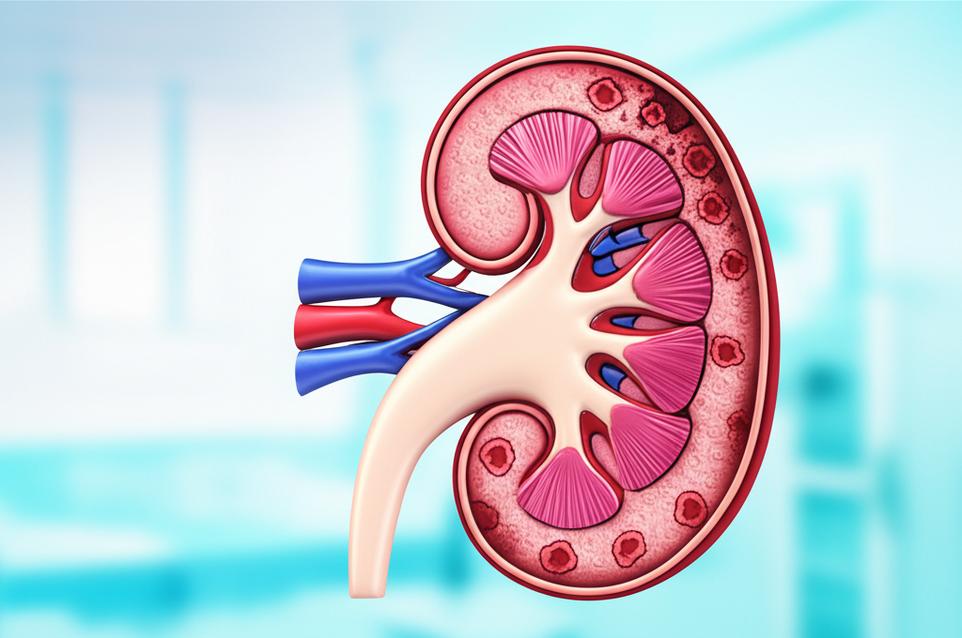

กลไกการทำงานของไตและการสะสมของความเสื่อม: ทำไมไตจึงสำคัญต่อชีวิตยืนยาว

ไตเป็นอวัยวะคู่ที่ซับซ้อน ทำหน้าที่เสมือนโรงงานบำบัดของเสียหลักของร่างกาย วันหนึ่งๆ ไตจะกรองเลือดมากถึง 120-150 ควอร์ต เพื่อกำจัดของเสียส่วนเกิน สารพิษ และรักษาสมดุลของน้ำ เกลือแร่ รวมถึงความเป็นกรด-ด่างในเลือด นอกจากนี้ ไตยังมีบทบาทในการผลิตฮอร์โมนที่ควบคุมความดันโลหิต สร้างเม็ดเลือดแดง และช่วยในการสังเคราะห์วิตามินดี ซึ่งจำเป็นต่อสุขภาพกระดูกและภูมิคุ้มกัน

เมื่อไตเริ่มทำงานผิดปกติ กระบวนการเหล่านี้จะหยุดชะงักลง โดยมักเกิดขึ้นอย่างช้าๆ และเงียบเชียบในระยะแรก ซึ่งเป็นที่มาของคำว่า ‘ฆาตกรเงียบ’ ในทางเวชศาสตร์ชะลอวัย เรามองว่าความเสียหายของไตมักเริ่มจากการสะสมของภาวะอักเสบเรื้อรัง (chronic inflammation) และความเครียดจากปฏิกิริยาออกซิเดชัน (oxidative stress) ซึ่งทำลายเซลล์ไตทีละน้อย ภาวะเหล่านี้มักมีต้นตอมาจาก: